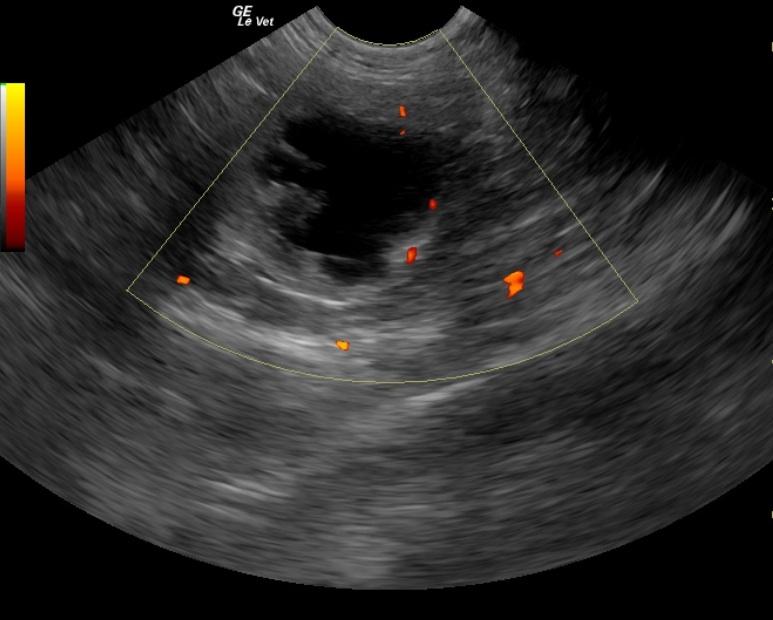

An 8-year-old female spayed DSH cat was presented for weight loss, anorexia, and weakness. The cat was currently on phenobarbital. The only significant abnormality on physical examination was right renomegaly. Urinalysis showed 3+ hematuria, 1+ proteinuria, and elevated microalbuminuria. Azotemia and hyperamylasemia were evident on serum biochemistry.

An 8-year-old female spayed DSH cat was presented for weight loss, anorexia, and weakness. The cat was currently on phenobarbital. The only significant abnormality on physical examination was right renomegaly. Urinalysis showed 3+ hematuria, 1+ proteinuria, and elevated microalbuminuria. Azotemia and hyperamylasemia were evident on serum biochemistry.